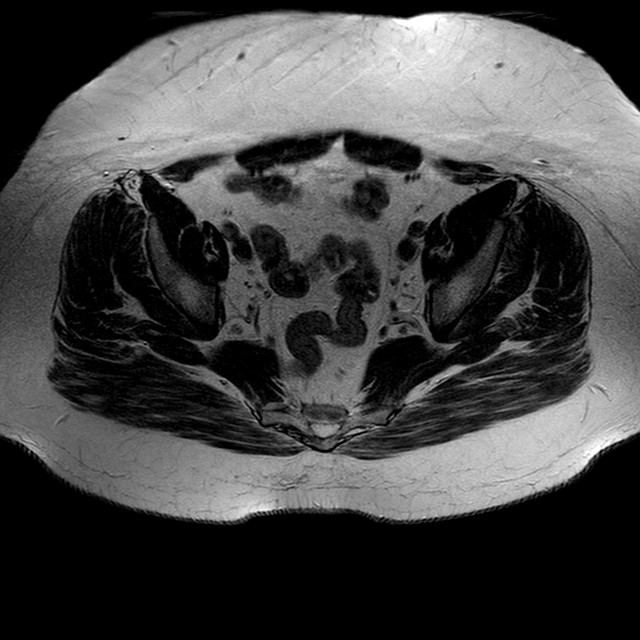

Esami: RMN BACINO

T2w TSE

Evidenti e simmetriche alterazioni osteofitosiche in regione coxo femorale con riduzione delle rime articolari. Degenerazione completa del cercine glenoideo. Non attuali segni di versamento articolare. Non segni di edema osseo che escludono attuale algodistrofia od osteonecrosi. Lieve e simmetrica riduzione del trofismo della muscolatura glutea.